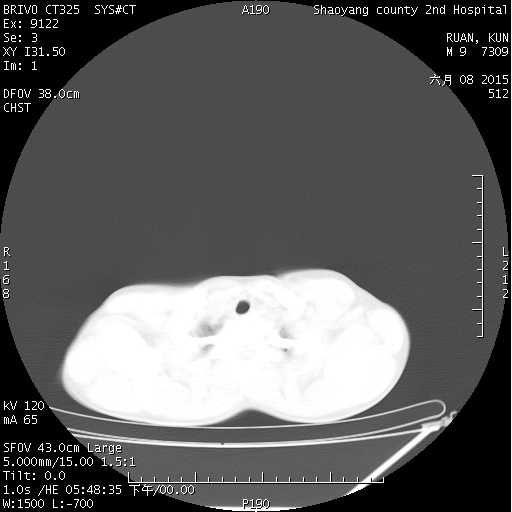

CT50591:胸,腹部急诊CT

本帖最后由 cefcmj 于 2015-6-8 22:09 编辑 外伤后呼吸困难1小时

两肺可见多发斑片状似磨玻璃样密度影,考虑创伤性湿肺,脾脏密度减低,胰头增大,结合临床。

双肺挫伤及双侧少量气胸。

符合创伤性湿肺,不除外肠破裂